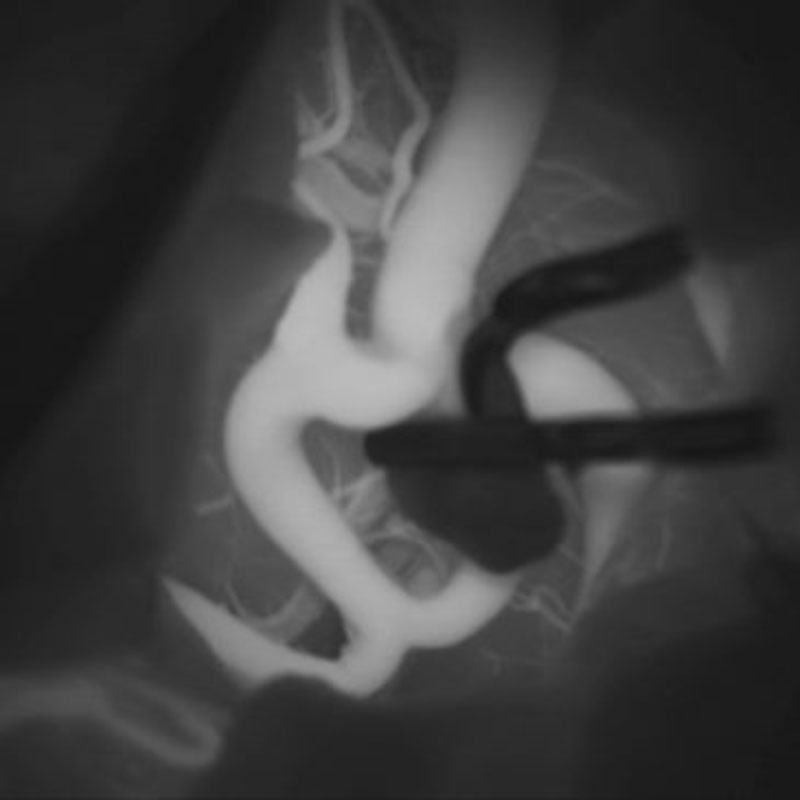

手術前

クリップ前

クリップ後

手術後